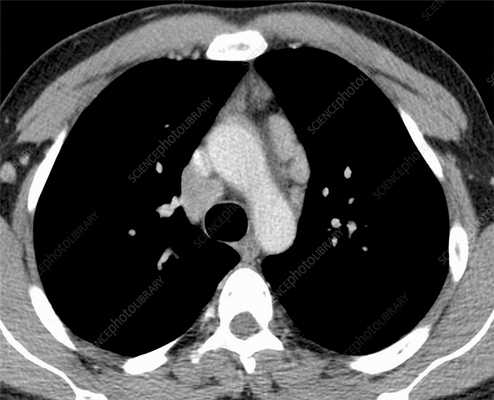

Лимфома легких на КТ

Признаки лимфомы легких особенно выражены на четвертой стадии заболевания, когда болезнь поражает дыхательный орган. На КТ при этом будут видны увеличенные лимфоузлы, формирующие цепочки, конгломераты. При этом у пациента может также наблюдаться отек легких. Однако высокая разрешающая способность КТ позволяет выявить лимфому на ранней, первой стадии.

На КТ лимфомы, как и любые уплотнения, визуализируются сравнительно более светлым цветом. В норме воздушная легочная паренхима практически однородного темного цвета. Иногда таких уплотнений несколько и они диссеминированны. Контуры лимфомы четкие и ровные. Вокруг патологических очагов обнаруживаются участки «матового стекла».